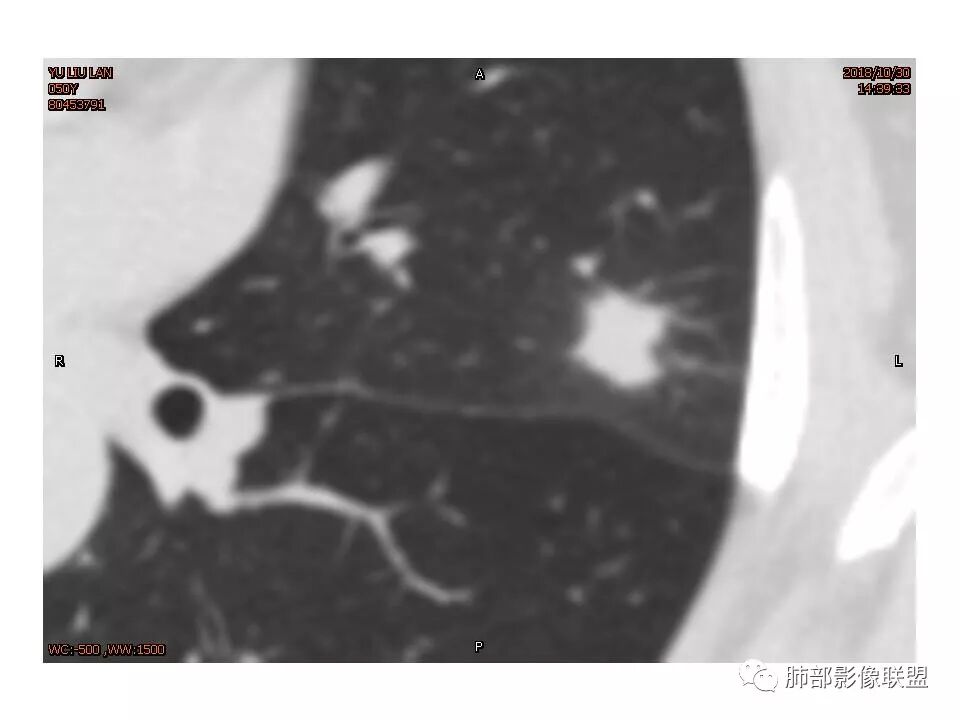

左肺上叶后段病灶,有毛刺,有胸膜牵拉,有血管滋养,好像还可以看见内部空泡,深分叶,边界比较清楚,考虑恶性肿瘤。

女,50。实性不规则结节,大小12*13mm,分叶、毛刺、胸膜凹陷,牵拉力强,增强渐进性强化,动脉期强化20,静脉期还有进一步强化。边缘强化,点状坏死。

其内血管被破坏。

左肺上叶实性不规则结节,有深分叶,短毛刺,有切迹,有血管集束,有胸膜牵拉,常规考虑恶性,鉴别炎性结节

女性,左上肺实性结节,有毛刺,有血管进入,边缘彭隆,月牙铲,深分叶,边界比较清楚,胸膜牵拉,考虑腺癌。

1.胸膜下略不规则实性密度结节影,孤立,缺乏典型深分叶,可见淡薄边界模糊磨玻璃晕,可见相对细长软毛刺。

2.如南边老师分析,病灶缺乏边缘膨隆优势,甚至部分平直内收。

3.病灶收缩力不强,整体强化程度不显著。

4.综上,病灶更符合炎性,如隐球菌感染等,而不大符合肺腺癌。具体到机化性肺炎略有些出乎预料。